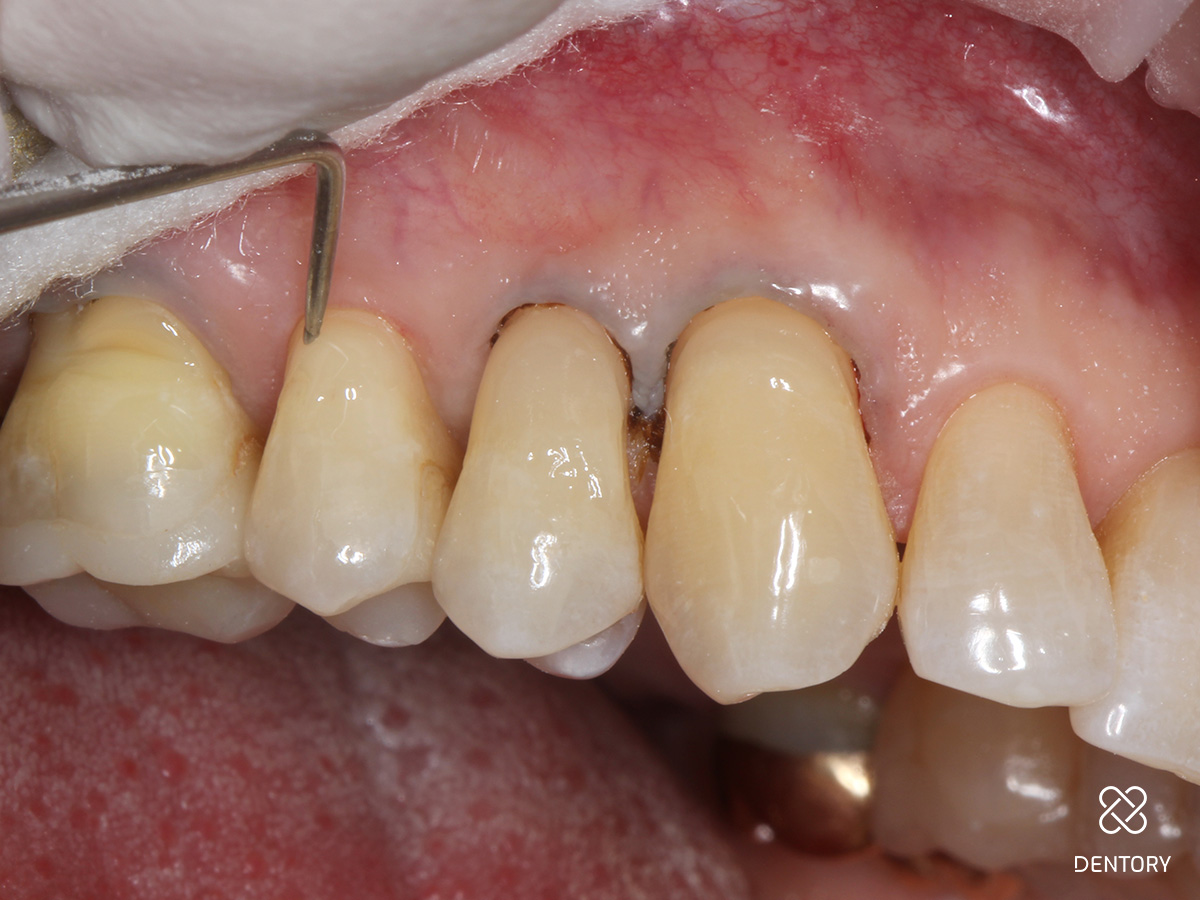

Abbildung 7

Entfernung der Bondingreste: Nach sicherem Durchhärten werden die eventuell überstehenden Füllungsränder oder Überreste des Bondings mit einer EVA-Feile vorsichtig entfernt - der Faden wird hierbei belassen, somit wird das Gewebe weniger verletzt. Mit einer Sonde wird getestet, ob alle Ränder einen glatten Übergang aufweisen. Achtung: Politur der Füllung mit Komposit-Polierern (Kelche eignen sich besonders gut).